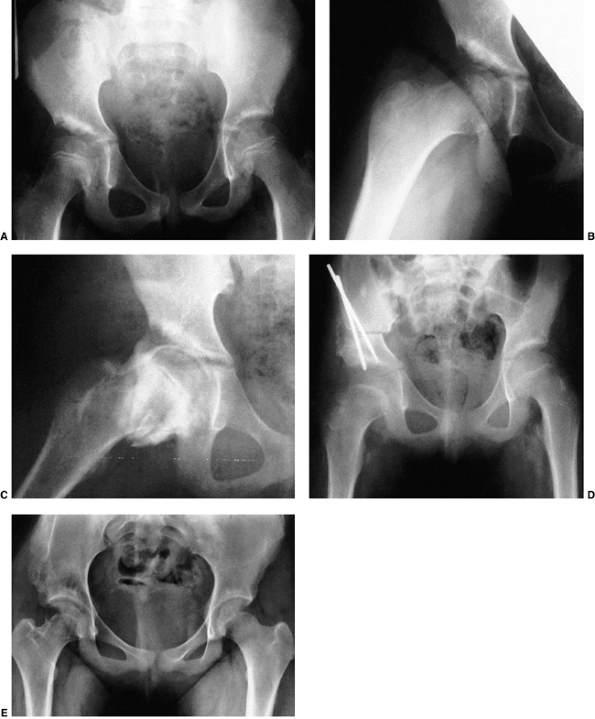

![]() |

Figure 24.23 Radiographic subluxation and dysplasia. A:

A 36-year-old woman with bilateral anatomically abnormal (dysplastic) hips. The left hip is radiographically subluxated, with the Shenton line disrupted, and the right hip is radiographically dysplastic, with the Shenton line intact. B: Seven years later, note the marked loss of joint space in the secondary acetabulum of the left hip and very early disruption of the Shenton line on the right. The right hip is asymptomatic, and the left hip is about to undergo total hip arthroplasty. |

Figure 24.24

Anteroposterior radiographs made after closed reduction of developmental dislocation of the hip that had been performed when the patient was 2 years and 4 months of age. A: Thirty-nine months after reduction, when the patient was 5 years and 7 months of age, the accessory centers of ossification are visible in the acetabular cartilage. B: Fifteen years after reduction, when the patient was 17 years of age, the Shenton line is intact and there is mild, acetabular dysplasia. C: Forty-two years after reduction, when the patient was 44 years of age, degenerative changes are present. D: Fifty-one years after reduction, when the patient was 53 years of age, the hip is subluxed and shows severe degenerative changes (Iowa Hip Rating, 48 of 100 points). The patient subsequently underwent total hip replacement. (From Malvitz TA, Weinstein SL. Closed reduction for congenital dysplasia of the hip: functional and radiographic results after an average of thirty years. J Bone Joint Surg Am 1994;76:1777.) |

Figure 24.25 A: Anteroposterior view of a 4-month-old girl with left hip dislocation and right hip subluxation. B: Abduction view. C: Abduction view at 7 months of age, 3 months after closed treatment. D: Anteroposterior view at 7 months of age, 3 months after closed treatment. E: Anteroposterior view at 7 years of age. Note the mild anatomic dysplasia of both hips. F:

Anteroposterior view at 15 years of age. Note the bilateral anatomic dysplasia. The right hip is radiographically dysplastic, and the left hip is radiographically subluxated. |